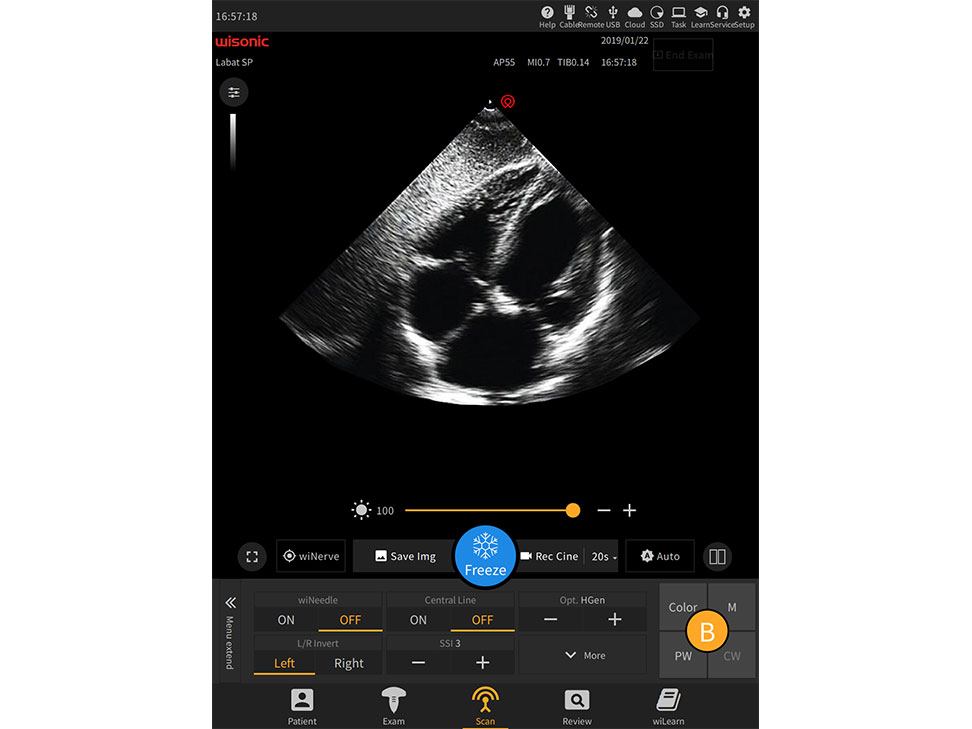

Overview

Videos

Images

Documents